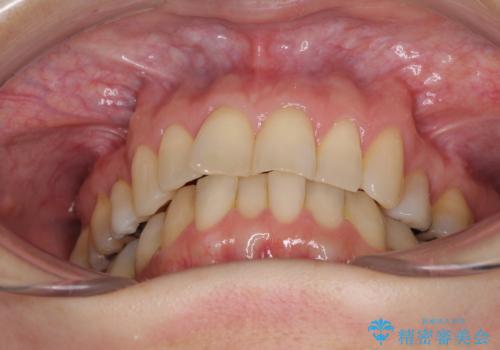

- 上下前歯の叢生を気にして来院された患者様です。

費用を抑え、期間もあまりかけずに治療をしたいとのことで、インビザライン・ライトを用いて矯正治療を行うこととしました。

矯正治療後には、下顎臼歯の目立つ銀歯をセラミックインレーにて修復治療を行いました。